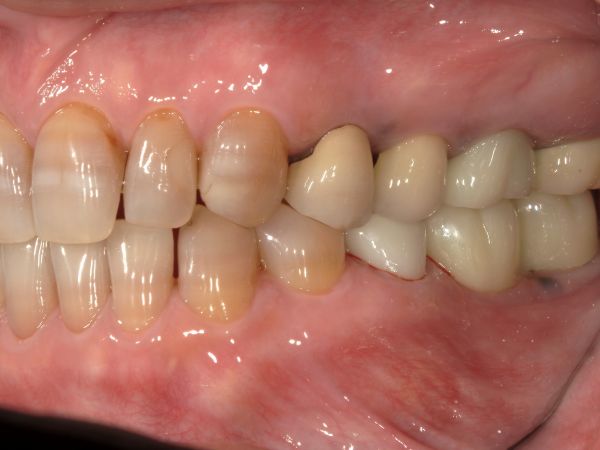

お口の中の状態の写真がこちらになります。

患者様は、インプラント治療を最初から希望されていらっしゃいましたが、全ての治療方法(入れ歯とインプラント)についてメリット・デメリットを説明させていただきました。患者様は極力違和感なく、しっかり噛めるインプラント治療をご希望されました。